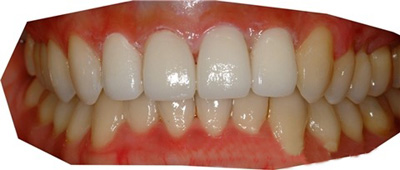

牙齿不齐矫正治疗后3个月,

就做了Laminate牙齿矫正和Laminate牙齿美白治疗。

治疗后的照片。

怎么样?变得很整齐了吧~

上牙4个,做了Laminate牙齿矫正治疗~